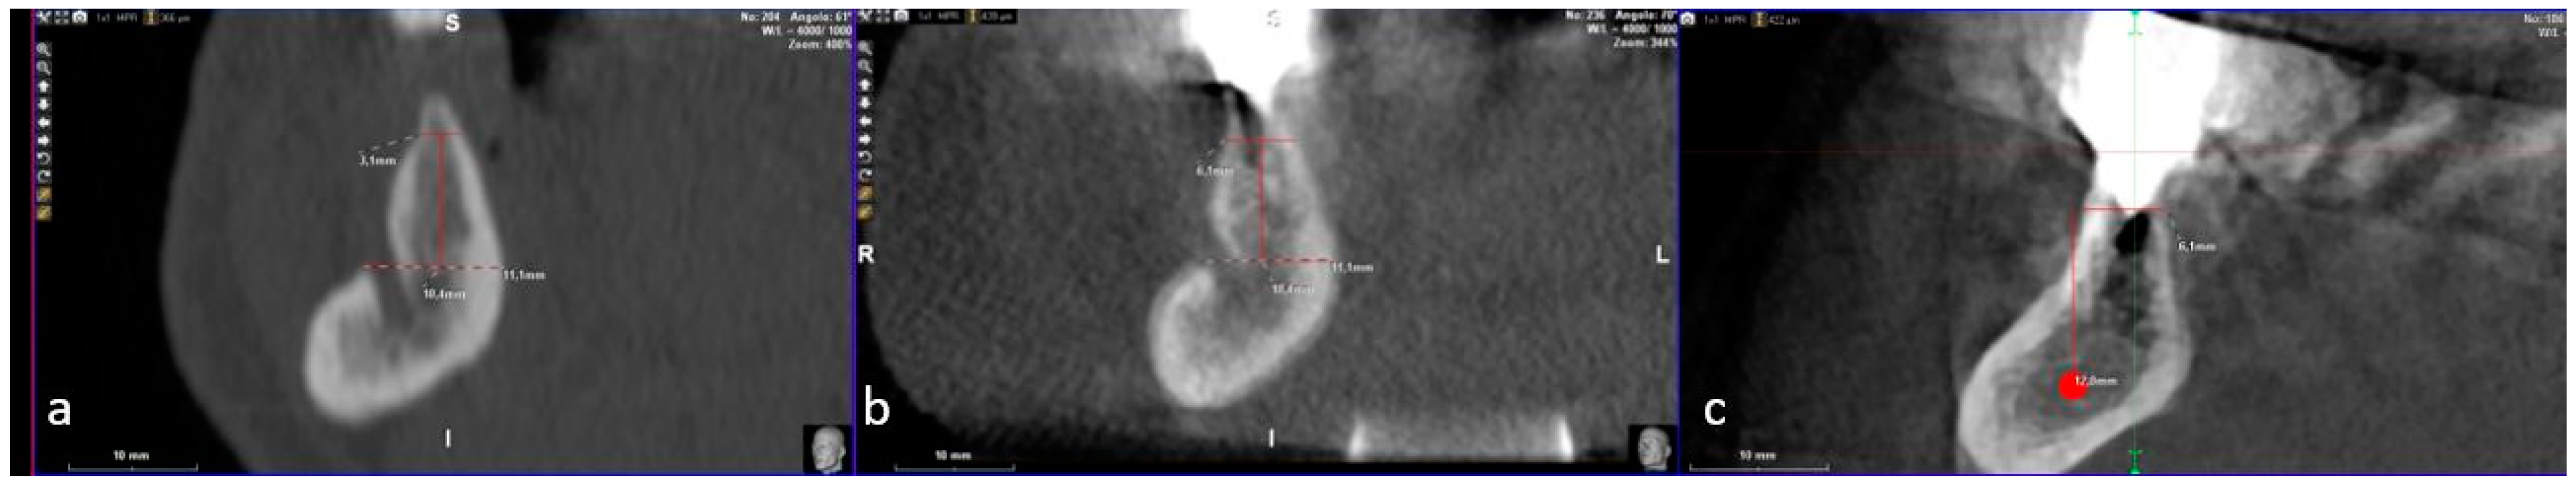

2. Case Description